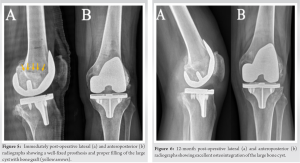

Extensive pre-operative planning was undertaken to address the technical challenges faced by this case. Planning objectives were to aim for a CR construct to minimize bone resection (Fig. 3). Alternative plans were made for stemmed posterior stabilized (PS), and total stabilized (TS) constructs with the use of femoral stem as needed. Pre-operative CT scanning was performed using the standard RA-TKA protocol (Stryker Mako, Mahwah, NJ). CT characterized a cystic lesion measuring 5 cm in its axial dimension. The resulting anatomical models demonstrated severe medial and lateral compartment osteoarthritis with genu valgus alignment.

Robotic-assisted TKA

After standard preparation for knee arthroplasty, the left knee was exposed using a limited anterior-midline incision. A median para-patellar arthrotomy was performed and standard procedure was followed to expose and register the knee for robotic arthroplasty. Assessment of the knee joint revealed severe end-stage articular damage with no remaining medial weight-bearing cartilage. The lateral compartment was severely eburnated with bone loss on the posterior tibia and posterior femoral condyles, resulting in the valgus deformity. Soft-tissue balance was performed, the pre-operative robotic plan was updated accordingly, and the robotic arm was utilized to execute the planned cuts. The patella was assessed and showed minimal degenerative changes, midline tracking, and no instability, so the decision was made not to resurface it. The bone defect in the lateral femoral condyle was then assessed and debrided from the membrane. The bone cyst was found to compromise 30–40% of the distal femoral cut. A decision had to be made between bone grafting and aiming for a CR construct or choosing a PS or TS construct with a stem. To avoid removing a substantial amount of host bone from a healthy medial and central aspects of the femur to prepare for the femoral box, we decided to proceed with bone grafting the cyst and placing a primary CR cementless femoral component (Fig. 4). The graft used consisted of autologous bone obtained from the cuts and 22 cc of a CSH/brushite/β-TCP graft containing 75% calcium sulfate (CaS) and 25% calcium phosphate (Pro-Dense™, Wright Medical Technology Inc., Memphis, TN) and it was placed in a doughy state (Fig. 4). Final implants were placed showing excellent press-fit, tracking, and stability with a 9-mm CS polyethylene. The extensor mechanism and capsule were anatomically repaired and range of motion was 0–135 without excessive stress. Standard skin closure was followed and the patient recovered adequately in PACU.

At 1-year follow-up, he reported no pain and no activity limitations. He has no effusion, tenderness, or instability. He has achieved 0°–120° knee range of motion without pain. Radiographs show well-fixed TKA with radiographic evidence of osteointegration and no osteolysis (Fig. 5 and 6).

Large subchondral cysts are common in osteoarthritic knees of RA patients [1]. Due to bone resorption caused by bone cysts and overall poor bone quality in these patients, treatment strategies should be tailored to optimize bone stock. A limited number of cases has been reported in the literature regarding the treatment of bone cysts in an osteoarthritic knee [16,17,18]. Moreover, only one case has been described using SBGS and TKA for the treatment of bony cysts. Thiery et al. [16] described a case of a male patient with a large lateral femoral condyle cyst. He was treated with curettage, filling with a CaS/HA bone graft substitute composed of 40% HA and 60% CaS (Cerament, Bonesupport, Lund, Sweden) and primary CR TKA. At 4 months post-operatively, they reported complete osseointegration of the bone graft. However, the patient developed arthrofibrosis and eventually required revision. In planning for TKA in patients with large bone cysts, management options usually involve revision implants with more invasive constructs [4,5]. Therefore, the use of robotic-assisted TKA may help to obtain reliable component positioning and optimal lower leg alignment. It is also possible to use a CT scan as a pre-operative tool to screen, detect, and delineate bony cysts to maximize bone preservation during surgical planning [19]. It should be noted that bone preservation was also a consideration in the decision to place a cementless CR prosthesis. Indeed, cementless prostheses have shown several advantages over cemented prostheses, such as better bone stock preservation, avoidance of cement debris, decreased operative time, and the potential value of osteointegration [20]. Moreover, selecting a femoral CR was preferred as PS designs which would have required a box cut (Fig. 4). As a result of this box cut, the intercondylar notch would have been further weakened and the cyst defect would have been connected, creating a massive bone defect and increasing the risk of periprosthetic fractures [21]. The use of robotic technology allowed the surgery to be performed without the placement of an endomedullary femoral rod, which is often necessary in manual TKA procedures. Performing this maneuver could have further debilitated or increased bone loss in the distal femur, thus jeopardizing the possibility of performing the surgery using primary components. Then, SBGS was chosen based on favorable clinical results and the mechanical properties that it provides once it sets [22,23,24]. For instance, Evaniew et al. [22] demonstrated rapid radiographic integration and early return to activities of daily living in patients with primary benign bone tumors. These observations are in agreement with our patient’s last follow-up, which showed excellent clinical outcomes and 1-year X-rays displaying a well-fixed prosthesis with graft oteointegration without impairing mechanical stability (Fig. 6). In sum, we presented the case of a rheumatoid patient with a large lateral femoral condyle cyst that was managed with robotic-assisted cementless CR TKA and augmentation with SBGS. Our approach limited the amount of healthy bone loss and ensured optimal component positioning and fixation in his altered anatomy. At 1-year follow-up, clinical and radiographic results are promising, suggesting that this approach may offer a bone-preserving and effective treatment option. Finally, CT-imaged robotic TKA offers the potential added benefit of screening bone cysts and thus planning a surgical approach in which bone preservation can be maximized.